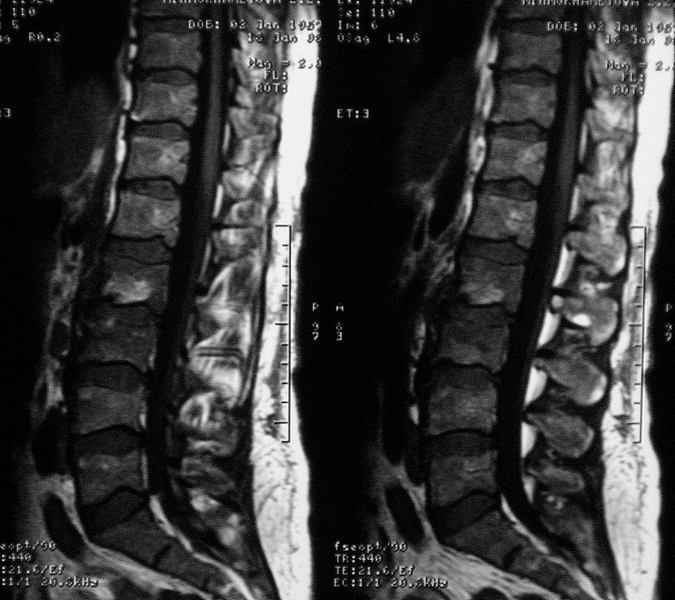

Отправляю MRI в динамике, снятые с пленки на фотоаппарат.

|

MRI через три недели

По данным представленных КТ и МРТ у больной имеется достаточно выраженная степень деструкции тел позвонков (около 30% общей костной массы тела позвонка), что определяет высокий риск возникновения патогических переломов и появления локальной кифотической деформации на этом уровне.

Данные МРТ выкладываешь некорректно - это не "контроль в динамике", а поход по Сусанинским местам, сравниваемые срезы за разные даты должны быть одинаковыми.